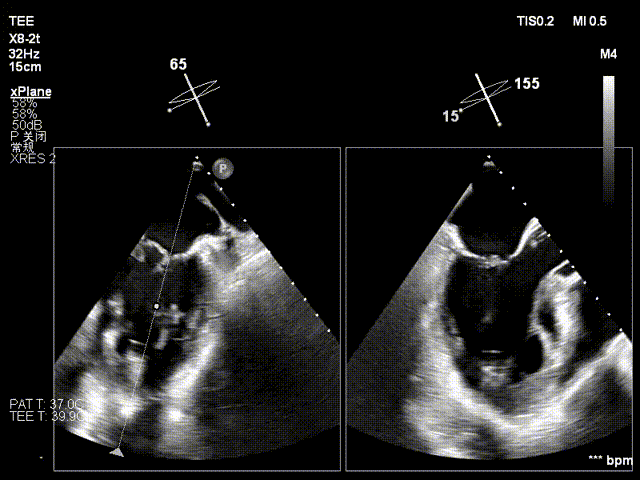

术中操作(关键步骤超声)

在全麻下,于心尖入路完成ValveClamp®装置植入。术中多学科团队密切配合,超声全程实时指导操作。最终,于2偏3区成功植入一枚Ⅲf夹子,一次夹合完成。前叶夹合量12mm,后叶夹合量10mm,反流降至1+,导管操作时间30分钟。术后平均跨瓣压差3mmHg。

术前反流 术后反流